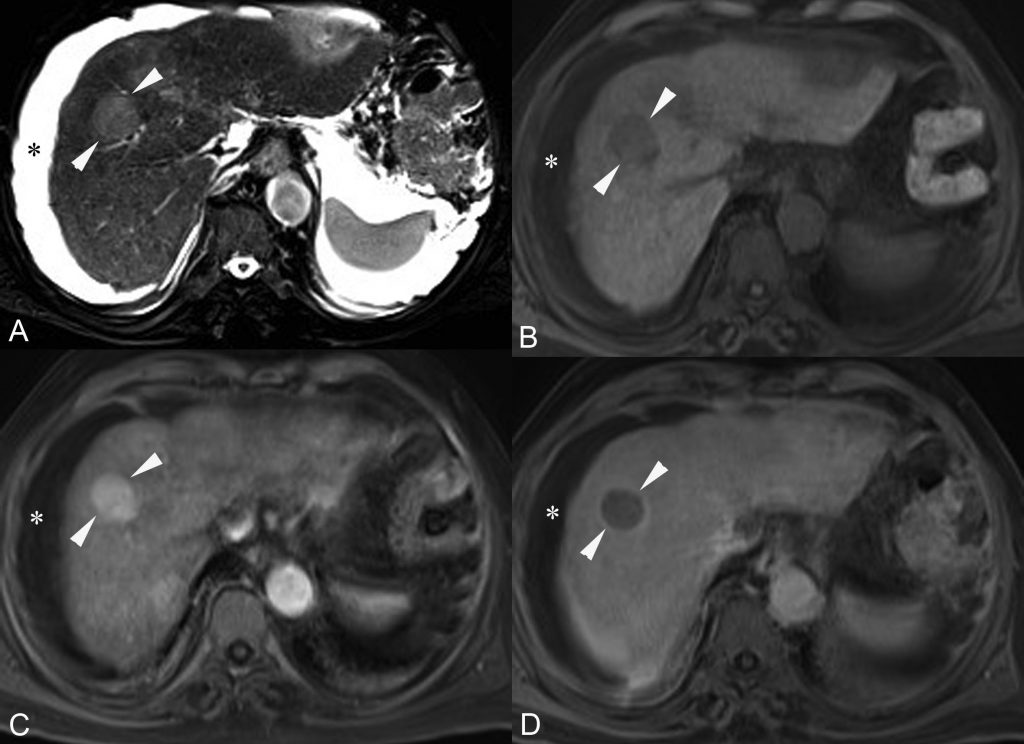

En IRM, la lésion est typiquement hypo-intense en pondération T1 et hyperintense en pondération T2 (figure 16.3). Elle peut être bien ou mal limitée.

Fig. 16.3. IRM d’un CHC dans un foie de cirrhose (flèches).

Le foie présente des signes de cirrhose et est entouré d’une ascite abondante (∗) en hypersignal sur les séquences en pondération T2 (A) et en hyposignal sur les séquences en pondération T1 (B, C, D). En pondération T2 (A), le CHC apparaît en discret hypersignal. En pondération T1 avant injection (B), il apparaît en hyposignal homogène. Après injection : au temps artériel (C), la lésion présente un rehaussement homogène, suivi d’un lavage très net au temps tardif (D). Le temps portal n’est pas figuré ici.

Source : CERF, CNEBMN, 2022.

Après injection de produit de contraste au scanner ou en IRM, le CHC est caractérisé par un rehaussement important au temps artériel suivi d’un lavage au temps veineux portal ou tardif (figures 16.2 et 16.3), c’est-à-dire que la lésion devient plus hypodense ou hypo-intense que le foie adjacent.